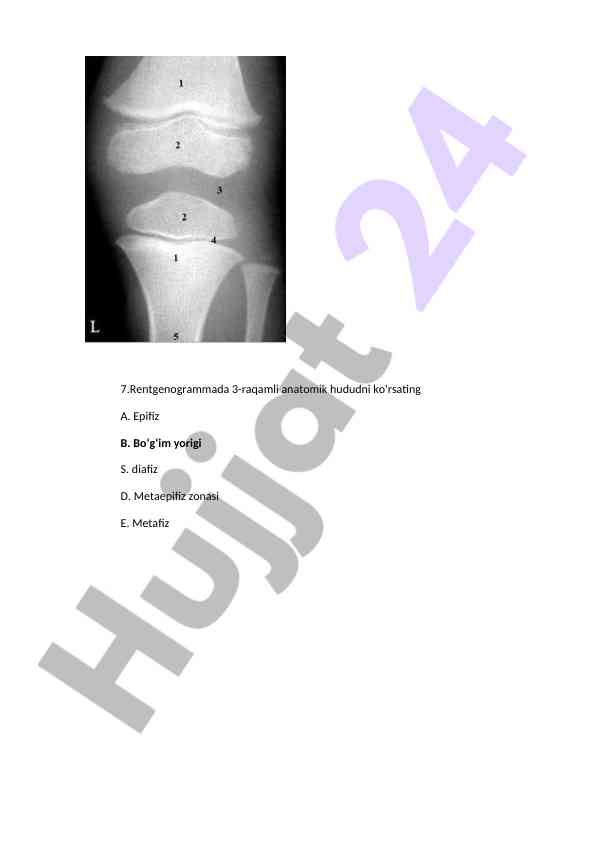

Rentgen tasvirlari bilan bog'liq diagnostik savollarga oid maslahatlar va javoblar, tibbiyotda rentgenografiya qo'llanilishi haqida ma'lumotlar.